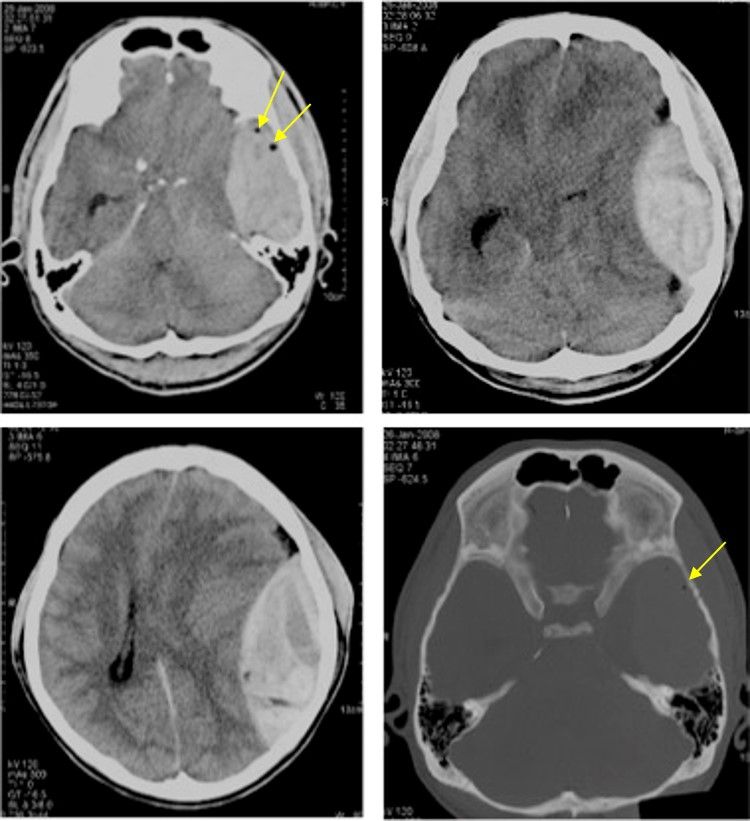

23-Year-Old Man Involved in Motor Vehicle Accident Post category:Spot Diagnosis Post published:August 22, 2023 Share on Facebook Share on X (Twitter) Share on Pinterest Share on Email Share on Reddit Axial non-contrasted CT scan of the brain with soft tissue and bone window A 23-year-old man was involved in motor vehicle accident. GCS on arrival at the emergency department was 13/15. An urgent non-contrasted CT brain was performed. What’s the diagnosis ? FULL CASE AND ANSWER Share on Facebook Share on X (Twitter) Share on Pinterest Share on Email Share on Reddit Read more articles Previous PostHypopigmentation and Hyperpigmentation on Sclerotic Skin Next PostRetiform Purpura and Coalescent Ulceronecrotic Lesions You Might Also Like Patient with Cyanosis of the Head, Neck, Upper torso, and Arms December 29, 2021 Patient with Progressively Worsening Abdominal Distention and Pain April 26, 2022 A 6-year-old Boy with Several Hours of Vomiting and Dyspnea March 20, 2022